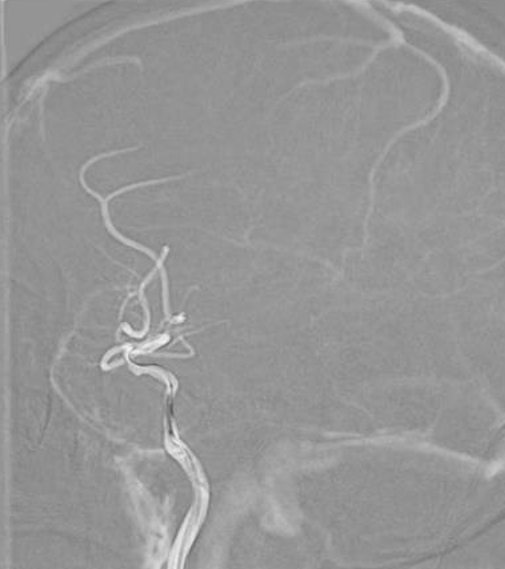

全脑及病变处不同体位造影。

导丝怎么扩【载药时代 球扩天下】NOVA DES®颅内药物洗脱支架在颈内动脉颅内段重度狭窄中的应用体会二例!_https://www.jmylbn.com_新闻资讯_第13张

导丝怎么扩【载药时代 球扩天下】NOVA DES®颅内药物洗脱支架在颈内动脉颅内段重度狭窄中的应用体会二例!_https://www.jmylbn.com_新闻资讯_第14张